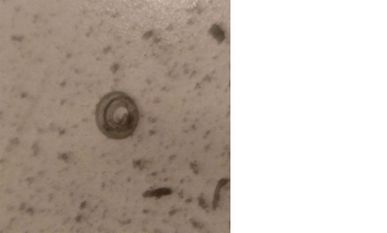

Trichinellen sind Fadenwürmer, die zum Beispiel im Fleisch von Wildschweinen vorkommen und beim Menschen zu milden bis schweren Erkrankungen (Durchfall, Fieber, Muskelschmerzen, Herzmuskelentzündungen) führen können.

Aus diesem Grunde werden alle Wildschweine und Hausschweine durch den Landkreis routinemäßig auf Trichinellen untersucht. Die mikroskopisch kleinen Parasiten lassen sich mit einer speziellen Analyse (Disgestionsmethode) nachweisen. Das Ergebnis der positiven Probe wurde durch das nationale Referenzlabor des Bundesinstitutes für Risikobewertung (BfR) bestätigt und ein sehr hoher Gehalt der Spezies „Trichinella pseudospiralis“ ermittelt.